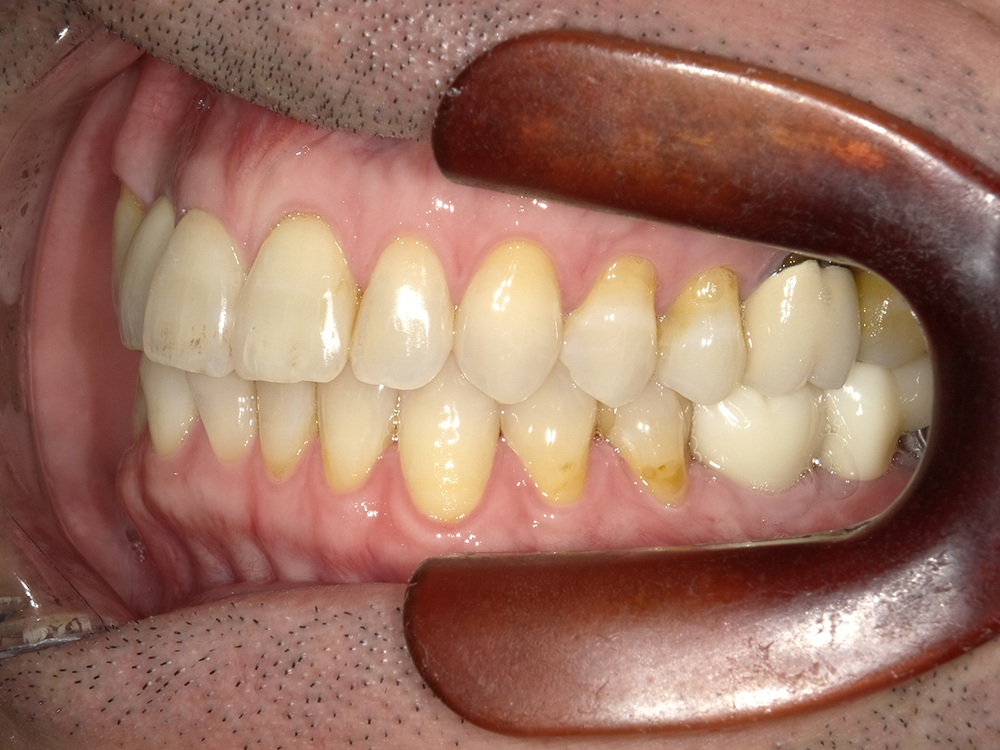

55歳 男性

- 主訴

- 前歯でしか咬めなく、食事を採るのに非常に困難で辛い

- 処置内容

- 上顎6本、下顎3本

- 治療費用

- 上顎:約230万(税込)下顎:約120万(税込)

- 治療期間

- 上顎:1年(仮歯まで8か月)下顎:8か月(仮歯まで5か月)

- リスク

- 上部構造物、仮歯の破折、術後の腫れ(3日)、人工歯根脱落リスクがあります